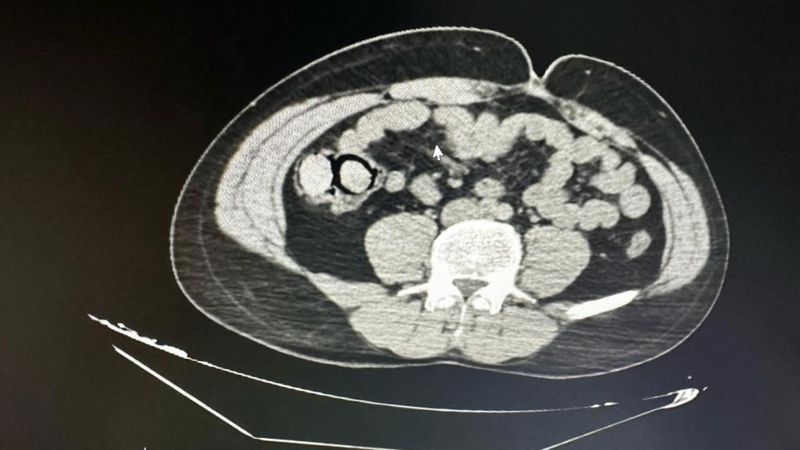

MİDESİNDEN 10 PAKET UYUŞTURUCU ÇIKTI

Gerçekleştirilen iç beden muayenesinde, 10 parça halinde toplam 113 gram metamfetamin ele geçirildi. Gözaltına alınan şahıslar, emniyetteki işlemlerinin ardından çıkarıldıkları mahkemece “uyuşturucu madde ticareti yapmak” suçlamasıyla tutuklanarak Elazığ Kapalı Ceza İnfaz Kurumu’na gönderildi.